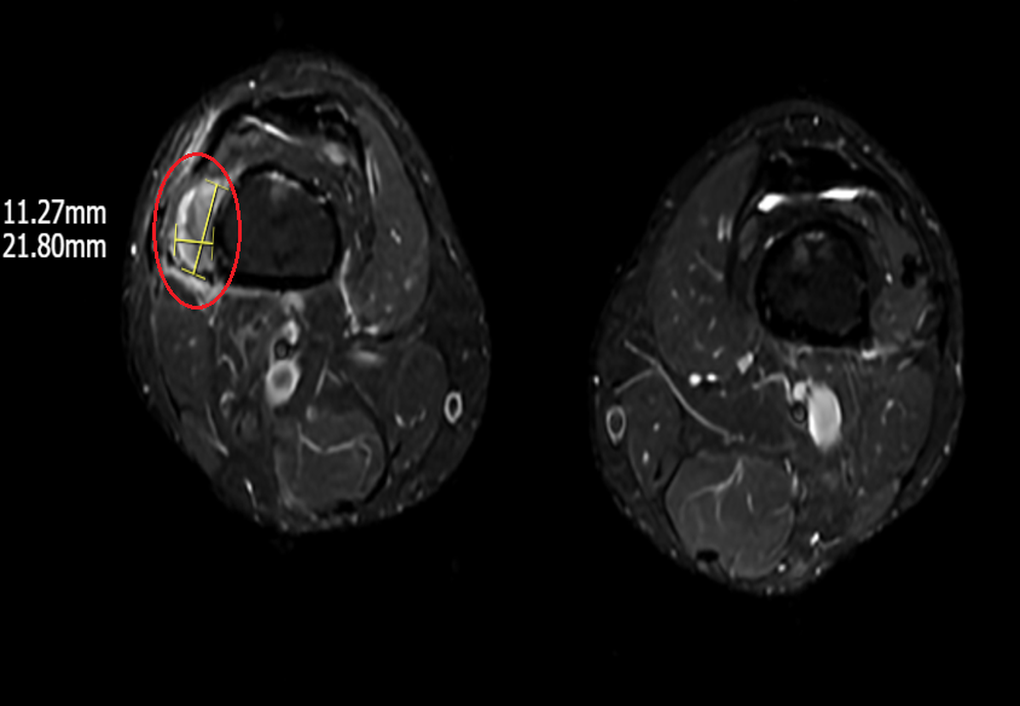

រូបភាពនៃដុំសាច់នៅតំបន់ជាលិកាទន់ក្រោមភ្លៅខាងស្តាំលើខ្សែភាពយន្ត MRI (រូបថត៖ BVCC)។

ដើម្បីបញ្ជាក់ពីរោគវិនិច្ឆ័យ ចាំបាច់ត្រូវកំណត់បរិមាណសន្ទស្សន៍ FGF23 ក្នុងឈាម ទោះជាយ៉ាងណាក៏ដោយ នៅប្រទេសវៀតណាមបច្ចុប្បន្នមិនមានការធ្វើតេស្តបែបនេះទេ។ ដូច្នេះហើយ យើងបានបញ្ជាឱ្យអ្នកជំងឺធ្វើការស្កែន PET/CT ពេញរាងកាយជាមួយនឹងសារធាតុវិទ្យុសកម្ម រួមជាមួយនឹង MRI និងអ៊ុលត្រាសោន ហើយទីបំផុតបានរកឃើញដុំសាច់ទំហំ 1-2cm នៅក្នុងជាលិកាទន់ក្រោមភ្លៅខាងស្តាំ"។